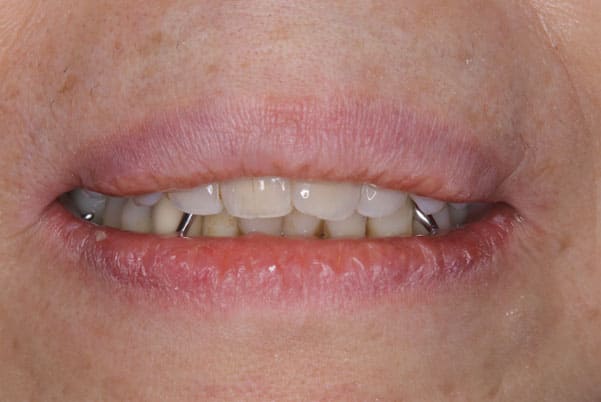

治療前後の口元の比較

こちらは、口を少し開いた時の治療前と治療後の

口元です。

正面から見た時にクラスプが目立たないように、

歯ぐきになじむ素材にて入れ歯を製作し、痛くなく自然に馴染み快適に生活を送れるようになりました。